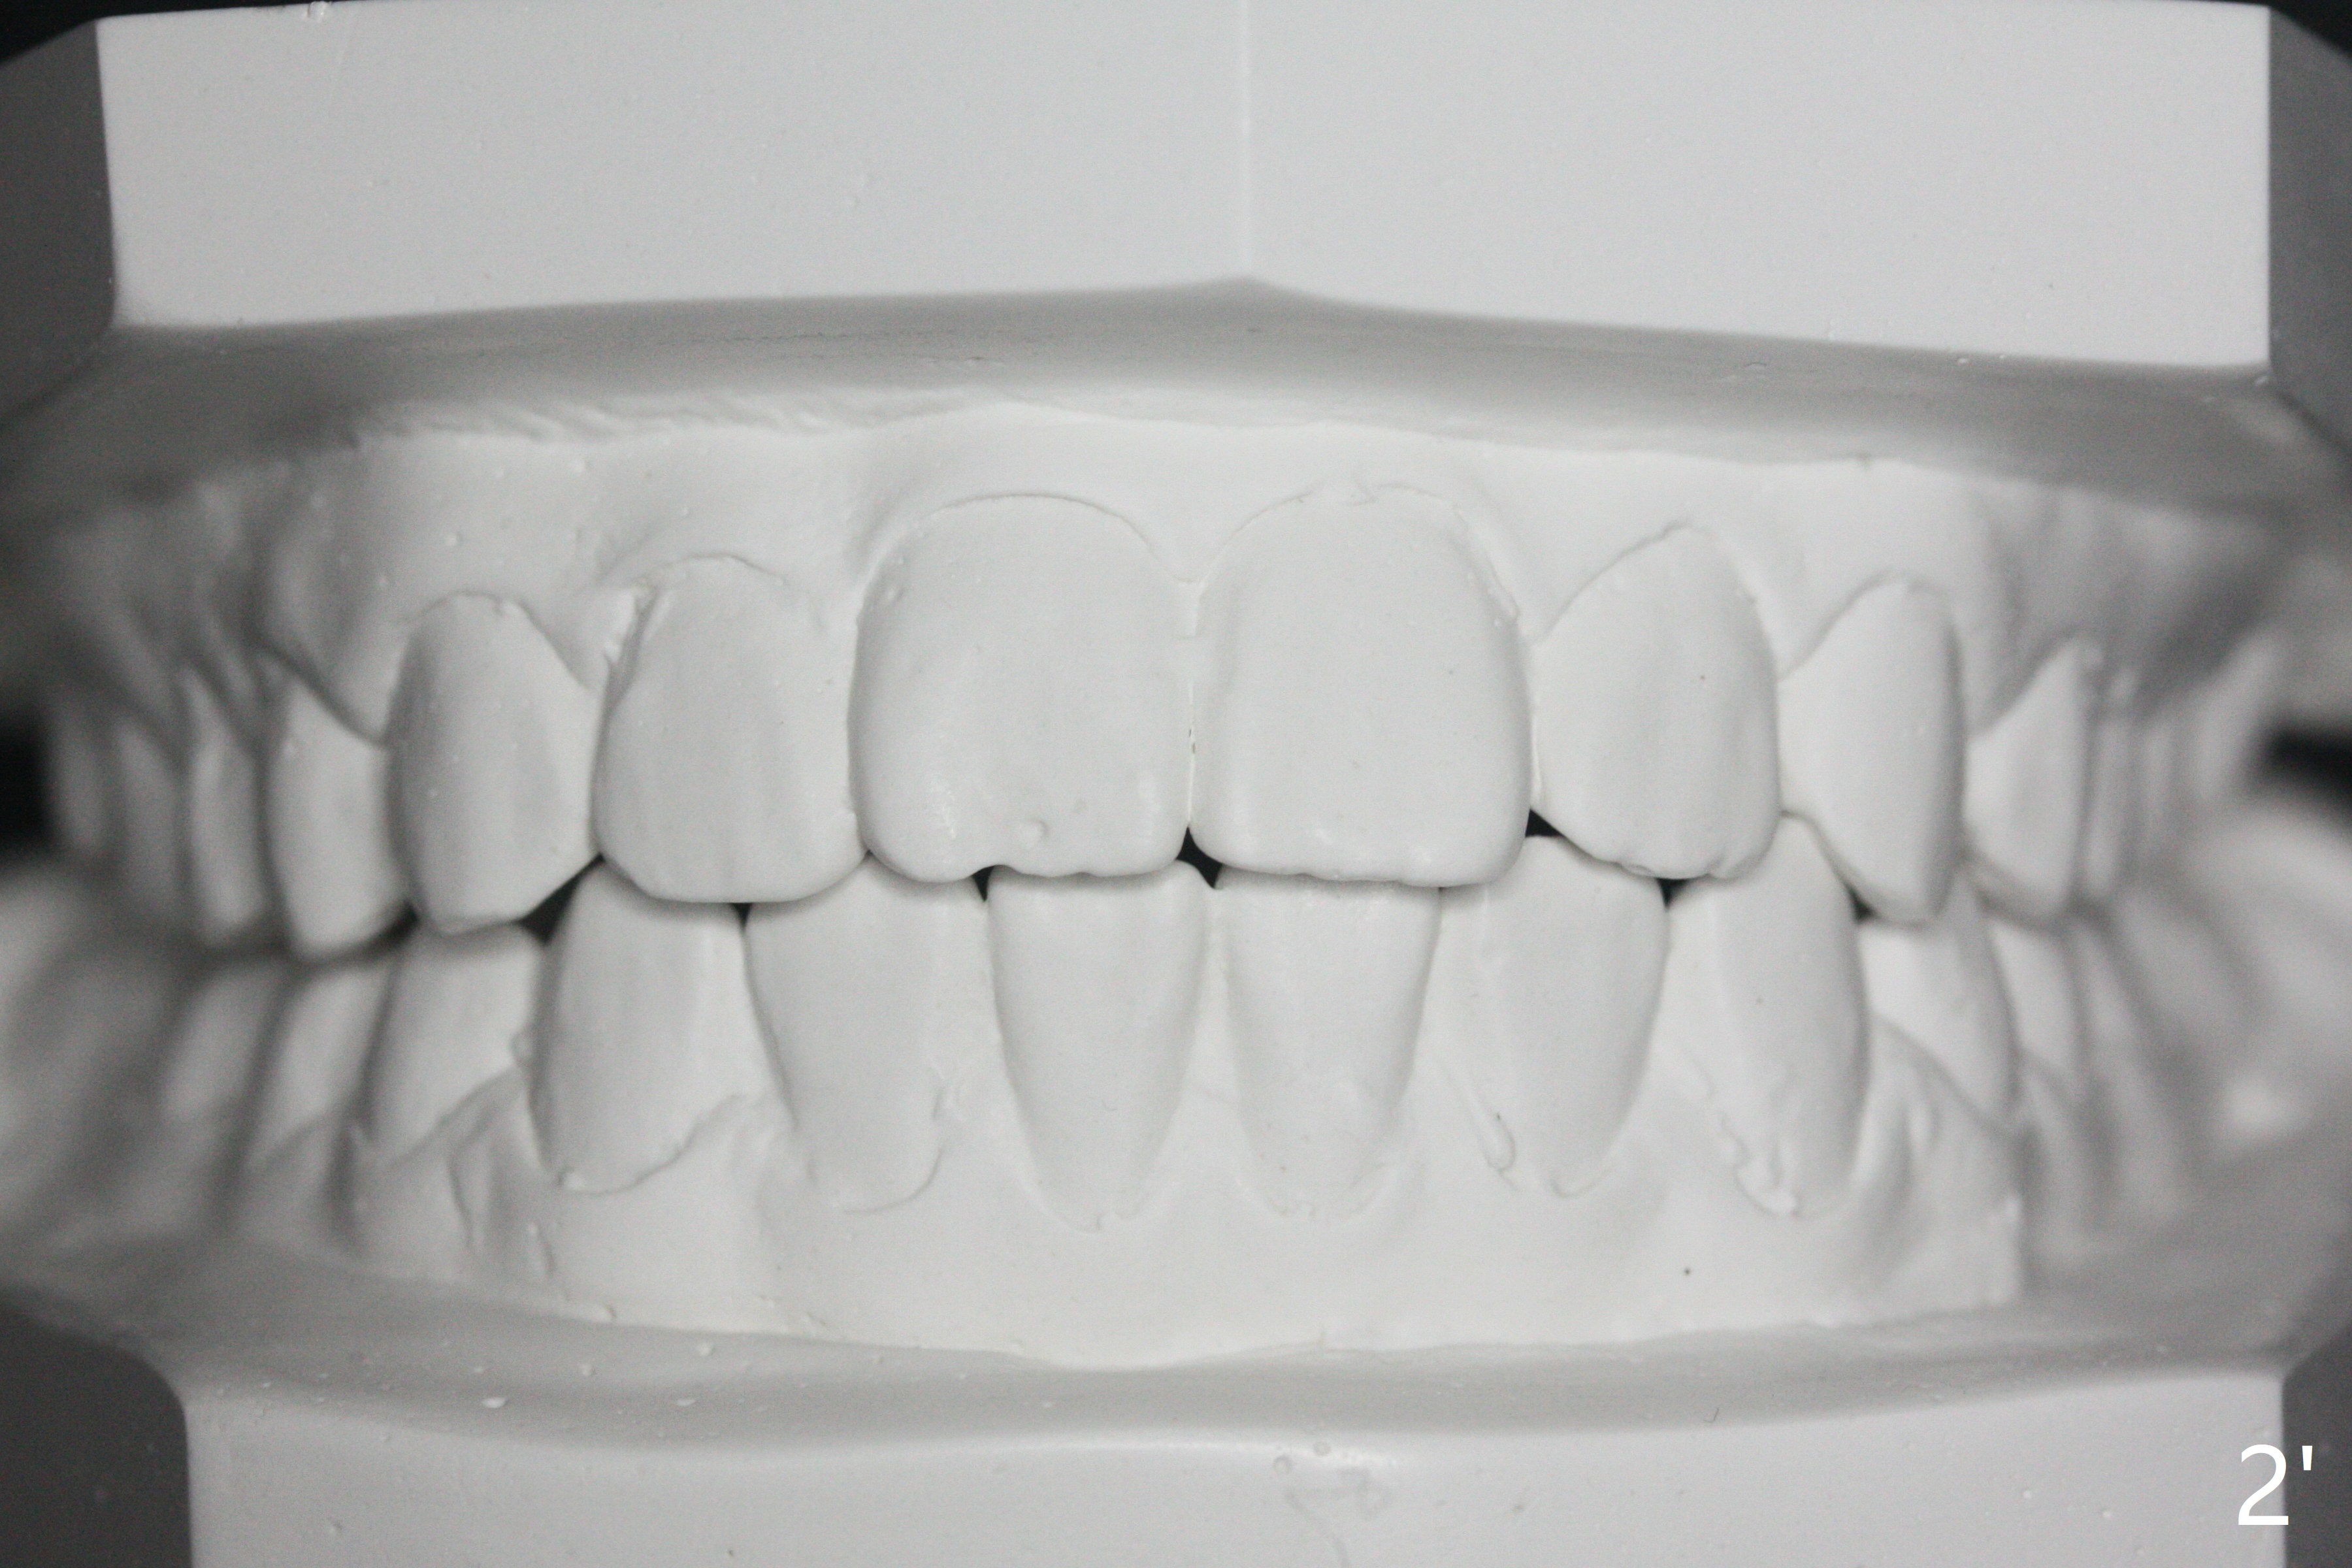

A 12-year-old woman has severe crowding including UL7 impaction (Fig.1-5), finishes non-extraction orthodontics at the age of 15 (Fig.1'-5') and returns for retainer remake at 19 (Fig.1''-5''). Four years post debanding, UL7 (Fig.4') seems to improve its position (Fig.4'').